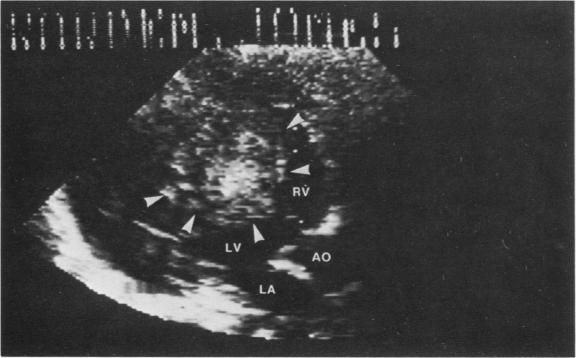

In the case presented here of a 2-month-old boy with symptoms of upper respiratory infection, the physical examination, chest X-ray film and electrocardiogram led us to suspect congestive heart failure caused by either a primary or infectious cardiomyopathy or by a structural left ventricular outflow tract obstruction. The echocardiographic findings were the first evidence to suggest the presence of an intracardiac tumor. A cardiac computerized axial tomography scan supported the findings. Operation was performed, but the tumor was unresectable. Biopsies of the mass revealed fibromatosis. The infant was discharged on diuretics, procainamide and propranolol. Approximately 3 weeks following discharge, while at rest, the child suddenly became unresponsive and could not be resuscitated. Postmortem examination verified the degree of precision that can be achieved by noninvasive techniques.